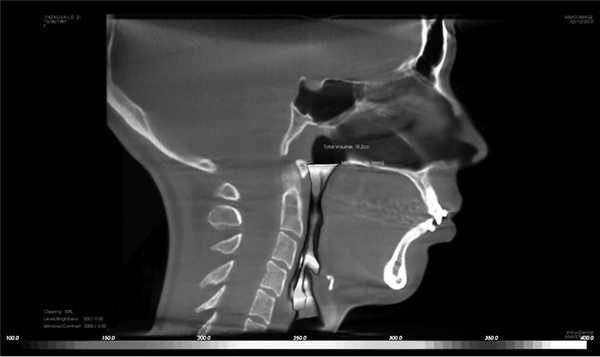

2. Дыхательные пути. В программе имеется визуальная шкала оценки степени сужения верхних дыхательных путей на уровне носо- и ротоглотки, основанная на исследовании David Hatcher. В норме площадь поперечного сечения дыхательных путей составляет 110—140 мм 2 . Объем дыхательных путей в данной программе рассчитывается от анатомической точки PNS до надгортанника. Черный, красный и оранжевый цвета обозначают сужение дыхательных путей (рис. 7) [10].

Рис. 7. Сужение дыхательных путей. Минимальная площадь поперечного сечения 26,1 мм 2 (норма 110—140 мм 2 ).

В норме язык должен занимать весь свод твердого неба; если на КЛКТ прослеживается пространство между языком и твердым небом, то это свидетельствует о неправильном его положении и функции, из-за чего происходит сужение дыхательных путей на уровне ротоглотки [11].